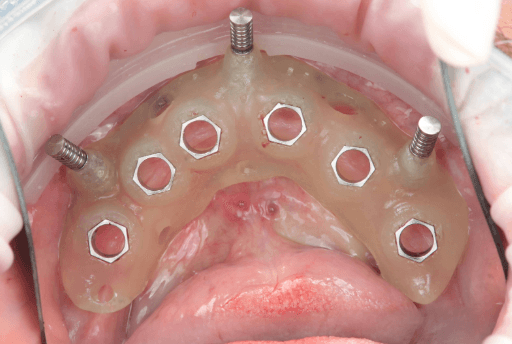

3.2 Post-Surgical Intraoral Scan

Scanning of implant position with scanbodies: Immediately after the implants were placed, the final implant position was captured using Apollo scanbodies and the intraoral scanner (Medit i900).

Apollo scanbodies in place.

Upper arch with Apollo scan bodies

Intraoral scan of upper arch with Apollo scanbodies

Photo of upper arch with Apollo scanbodies

Intraoral scan of lower arch with Apollo scanbodies

Upper arch from intraoral clinical situation digitized using the Apollo scanbodies and intraoral scanner.

Lower arch from intraoral clinical situation digitized using the Apollo scanbodies and intraoral scanner.